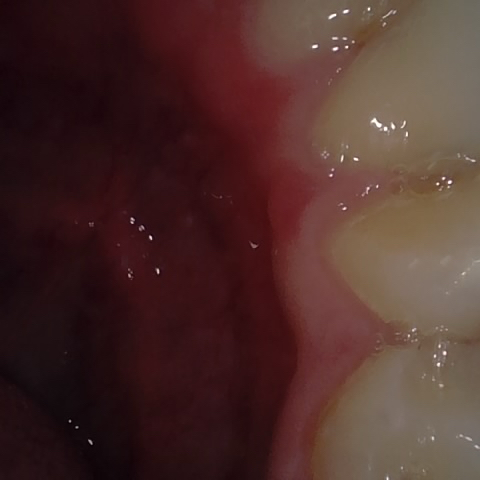

Annotated as "Bad"